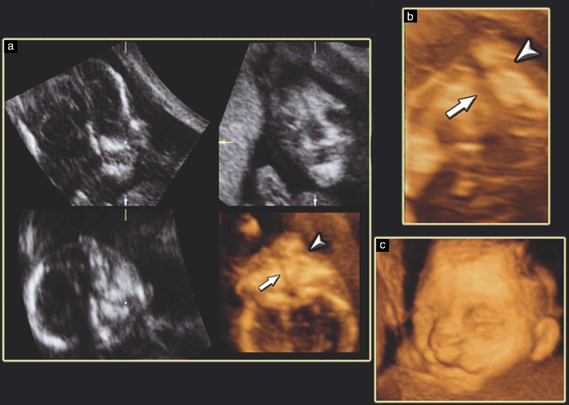

Ultrasound examination can detect clefts of the lip and alveolus unlike cleft palate, which is difficult to diagnose through routine screening.3

2 dimension ultrasound in conjunction with 3D ultrasound improves the detection rate for fetal cleft lip and palate, compared with 2Dultrasound alone.6